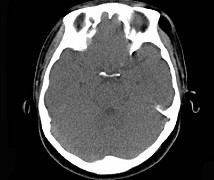

女,31岁,在左眶外上缘发现一包块,质软,余所见无明显异常。如图所示病灶应诊断为 ( ) 2YJB-16841.jpg 2YJB-16842.jpg 2YJB-16843.jpg 2YJB-16844.jpg

题型: 单选题 分类: 眼科学

• A.畸胎瘤

• B.错构瘤

• C.脂肪瘤

• D.表皮样囊肿

• E.淋巴管瘤